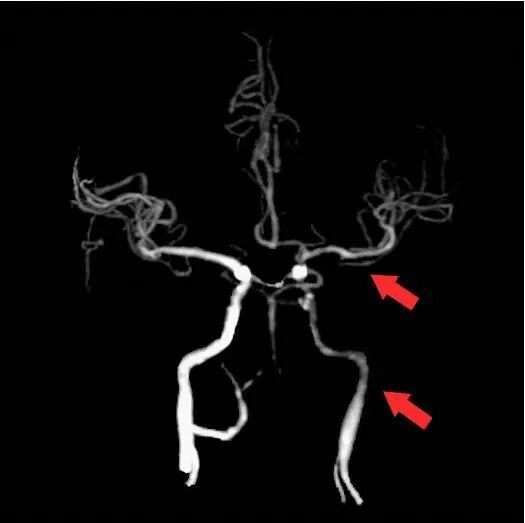

15min后,观察正侧位、3D旋转,可见狭窄较前明显改善。

复查颅脑CTA及CTP,改善明显。